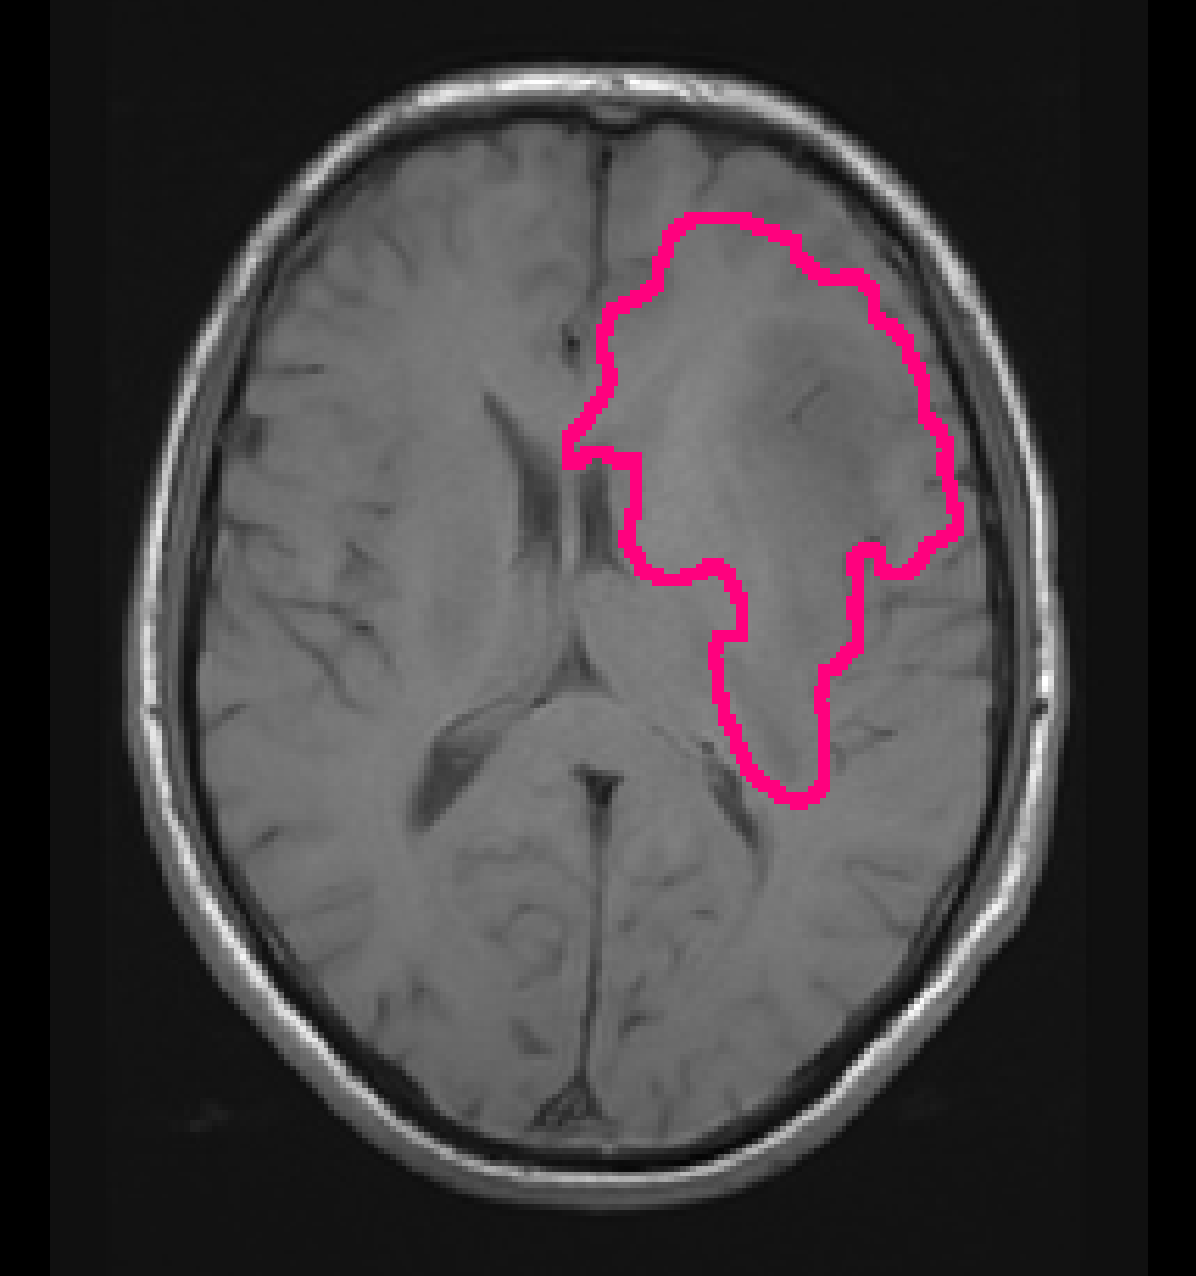

For the automatic segmentation, we achieved a mean DICE score of 0.84, a mean Hausdorff distance of 18.9 mm, and a mean volumetric similarity coefficient of 0.90. Figure 4 shows boxplots of the DICE scores, Hausdorff distances, and volumetric similarity coefficients for the different patients in the test set. In Appendix B we show five patients that were randomly selected from both the TCGA-LGG and TCGA-GBM data collections, to demonstrate the automatic segmentations made by our method.

To demonstrate the automatic segmentations made by our method, we randomly selected five patients from both the TCGA-LGG and the TCGA-GBM dataset. The scans and segmentations of the five patients from the TCGA-LGG dataset and the TCGA-GBM dataset are shown in Figures 12 and 14, respectively. The DICE score, Hausdorff distance, and volumetric similarity coefficient for these patients are given in Table 7. The method seems to mostly focus on the hyperintensities of the T2w-FLAIR scan. Despite the registrations issues that can be seen for the T2w scan in Figure 14(d) the tumor was still properly segmented, demonstrating the robustness of our method.